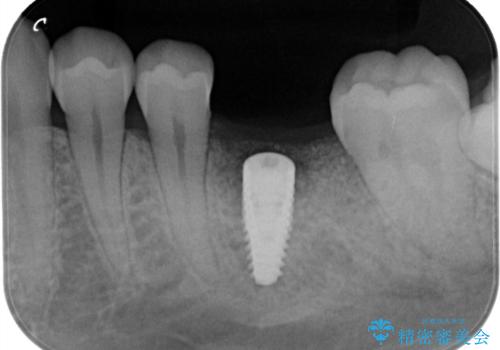

- 他院で抜歯と言われ、今後どうしたらいいのかを相談された患者様です。

抜歯を行った後は、Br、義歯、インプラント、何もしないという選択肢のメリットデメリットを説明させていただき患者様がインプラント治療を希望されたので今回治療させていただくことになりました。

歯のなかったところをインプラント治療を行うことによってまた噛める喜びを感じていただけて良かったと思っております。